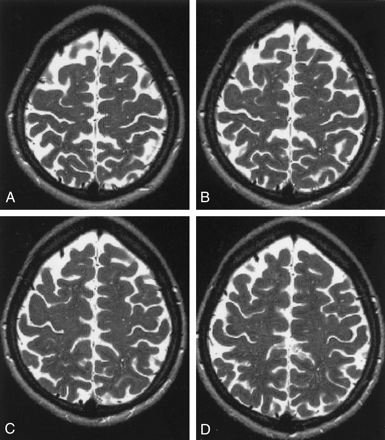

The VRSs resembled small isointense sandlike grains within the white matter on T1- and T2-weighted images (Fig 2). The appearance of VRSs in consecutive high-convexity T2-weighted images is demonstrated in Figure 3.

Axial high-convexity MR images show grade 3 VRSs with a sandlike appearance.

A, T2-weighted image (5500/128).

B, T1-weighted image (550/12).

Consecutive axial high-convexity T2-weighted MR images (5500/128) show VRSs. Image in A is most superior; image in D, most inferior.